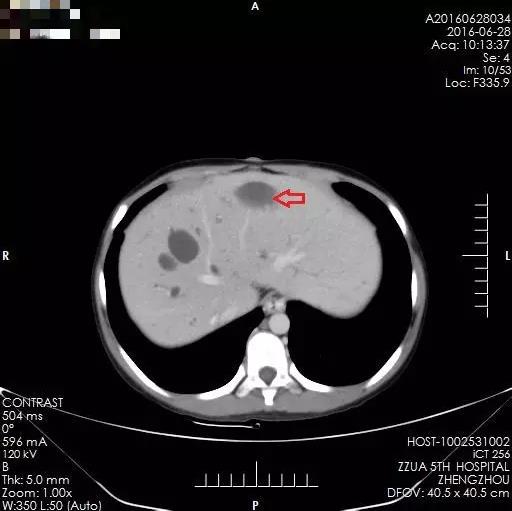

术后2年,箭头所示为肝肿瘤切除后

之后的两年里,小夏定期来院复查,肝脏内无肿瘤复发表现,病情平稳。然而,虽然解决了肝脏内肿瘤问题,但小夏的肝脏存在先天性胆管扩张、肝硬化及门静脉高压,食管下段、胃底及腹腔内有明显的静脉曲张,门静脉高压仍然缓慢进展,两年后因上消化道出血再次来到郑州大学五附院。完善相关检查,肝内未见肿瘤复发迹象,但门静脉高压症状明显,为预防再次消化道出血,缓解门静脉高压,经全面术前评估,小夏于2016年8月接受了全麻下行食管下段、胃底贲门周围血管离断术、脾动脉结扎、脾肺分流术。手术顺利完成,术后恢复良好,无任何并发症,术后定期复查,肝内未见肿瘤复发表现,门静脉高压有所缓解,病情平稳,小夏未再出现呕血。